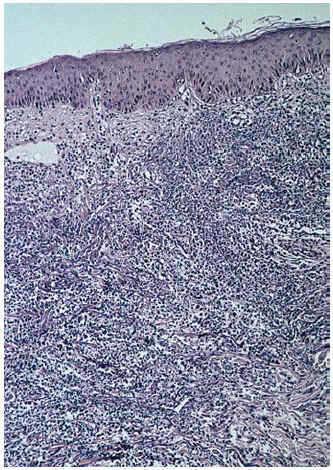

La biopsia de una lesión reciente, localizada en muslo izquierdo, reveló un infiltrado neutrofílico masivo y polvillo nuclear ocupando difusamente toda la dermis desde el cuerpo papilar hasta la hipodermis (fig. 6). En el seno del infiltrado neutrofílico se podían encontrar algunos vasos con necrosis fibrinoide de la pared (fig. 7). La inmunofluorescencia directa fue negativa. Los cultivos de una porción de biopsia para bacterias, hongos y micobacterias no revelaron crecimiento patógeno.

Fig. 6.--Aspecto histológico general.